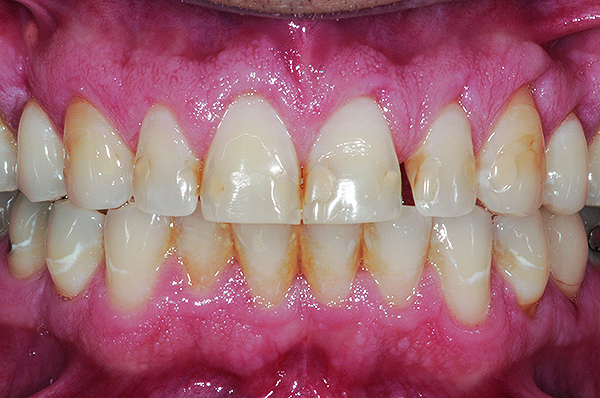

Fig 5. Preoperative view of patient requiring esthetic changes up to at least the bicuspids (Fig 5); postoperative view with CL-I feldspathic porcelain veneers up to the first bicuspid (Fig 6).

Figure 5

Fig 6. Preoperative view of patient requiring esthetic changes up to at least the bicuspids (Fig 5); postoperative view with CL-I feldspathic porcelain veneers up to the first bicuspid (Fig 6).

Figure 6

Class I (CL-I) powder and liquid porcelains are created from materials primarily containing silicon dioxide and possess a glassy matrix and varying amounts of a crystalline phase within the glassy matrix (eg, Creation Porcelain, Jensen Dental, www.jensendental.com; Ceramco 3, DENTSPLY International, www.dentsply.com; EX-3, Kuraray Noritake Dental, Inc., www.kuraraynoritake.com). The CL-I group includes feldspathic porcelains, referred to as such because they were originally—and some continue to be—made from naturally occurring feldspars (ie, aluminosilicates composed of assorted quantities of potassium, sodium, barium, or calcium).9,17 Several feldspathic material options are available on the market today (eg, VITA VM 13, VITA Zahnfabrik, www.vita-zahnfabrik.com; Vintage Halo, Shofu, www.shofu.com) (Figure 1 through Figure 3).

CL-I materials are fabricated by hand (Figure 4); they are the most conservative and generally the most translucent ceramic materials, but they are also the weakest.9,10,18 The material’s high translucency and esthetics create the illusion of natural teeth.9 Powder/liquid porcelain materials are ideal for cases in which significant enamel remains and/or there is healthy tooth structure on the teeth (ie, 50% or more remaining enamel on the tooth), and 50% or more of the bonded subst rate is enamel, and 70% or more of the margin is in the enamel. Feldspathic porcelain restorations that are bonded to primarily enamel substrates have proven to be highly successful long term.19

Powder/liquid porcelains demonstrate high esthetics and workability, and because they can be layered very thinly and placed directly on the enamel, they are considered the most conservative of the metal-free ceramic classes.10 CL-I porcelains require a thickness of 0.2 mm to 0.3 mm for each shade change.20,21

This class of materials is generally indicated for anterior restorations but can also be used for the occasional bicuspid and rare molar, providing all parameters are at a very low risk level (Figure 5 and Figure 6).